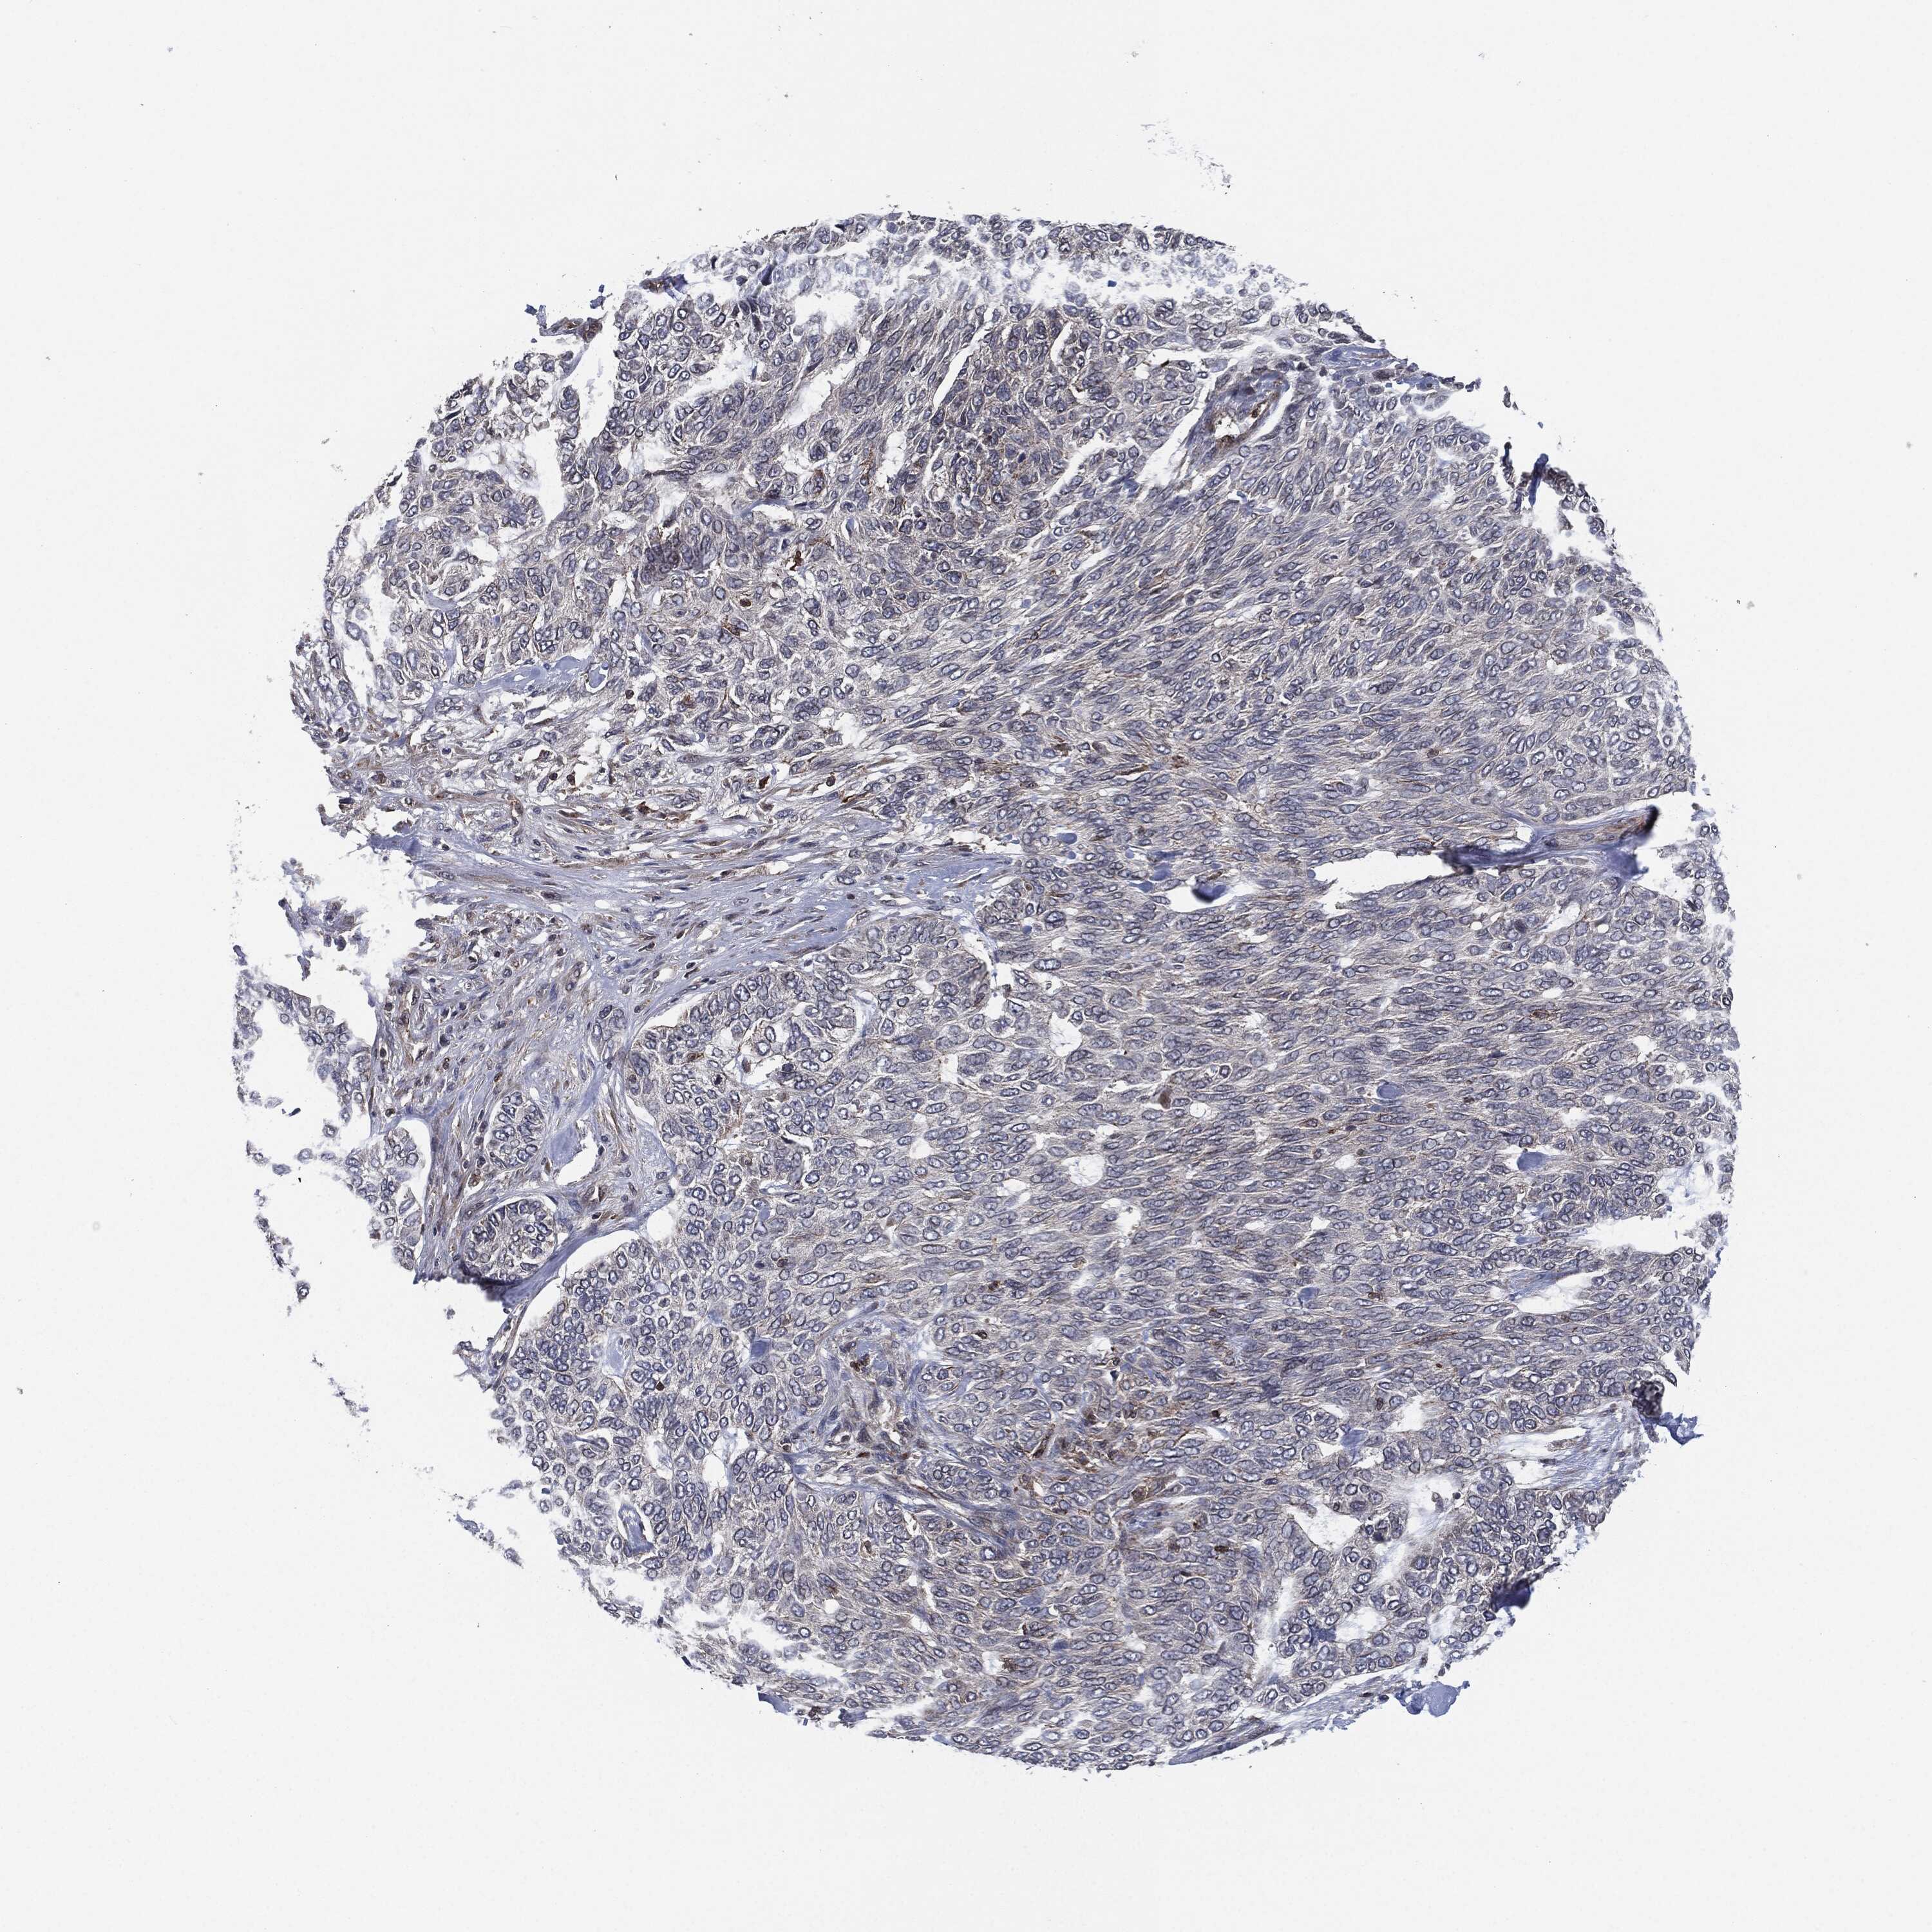

SKIN CANCER - Protein expressioni

A mouse-over function shows sample information and annotation data. Click on an image to view it in a full screen mode. Samples can be filtered based on level of antibody staining by selecting one or several of the following categories: high, medium, low and not detected. The assay and annotation is described here.

Antibody stainingi

Antibody staining in the annotated cell types in the current human tissue is reported as not detected, low, medium, or high, based on conventional immunohistochemistry profiling in selected tissues. This score is based on the combination of the staining intensity and fraction of stained cells.

Each image is clickable and will lead to virtual microscopy that enables deeper exploration of all samples and also displays staining intensity scores, fraction scores and subcellular localization as well as patient and tissue information for each sample.

Antibody HPA038838

Antibody HPA046727

Staining

High

Medium

Low

Not detected

Intensity

Strong

Moderate

Weak

Negative

Quantity

>75%

75%-25%

<25%

None

Location

Nuclear

Cytoplasmic/membranous

Cytoplasmic/membranous,nuclear

Basal cell carcinoma

Squamous cell carcinoma, NOS

Squamous cell carcinoma, metastatic, NOS